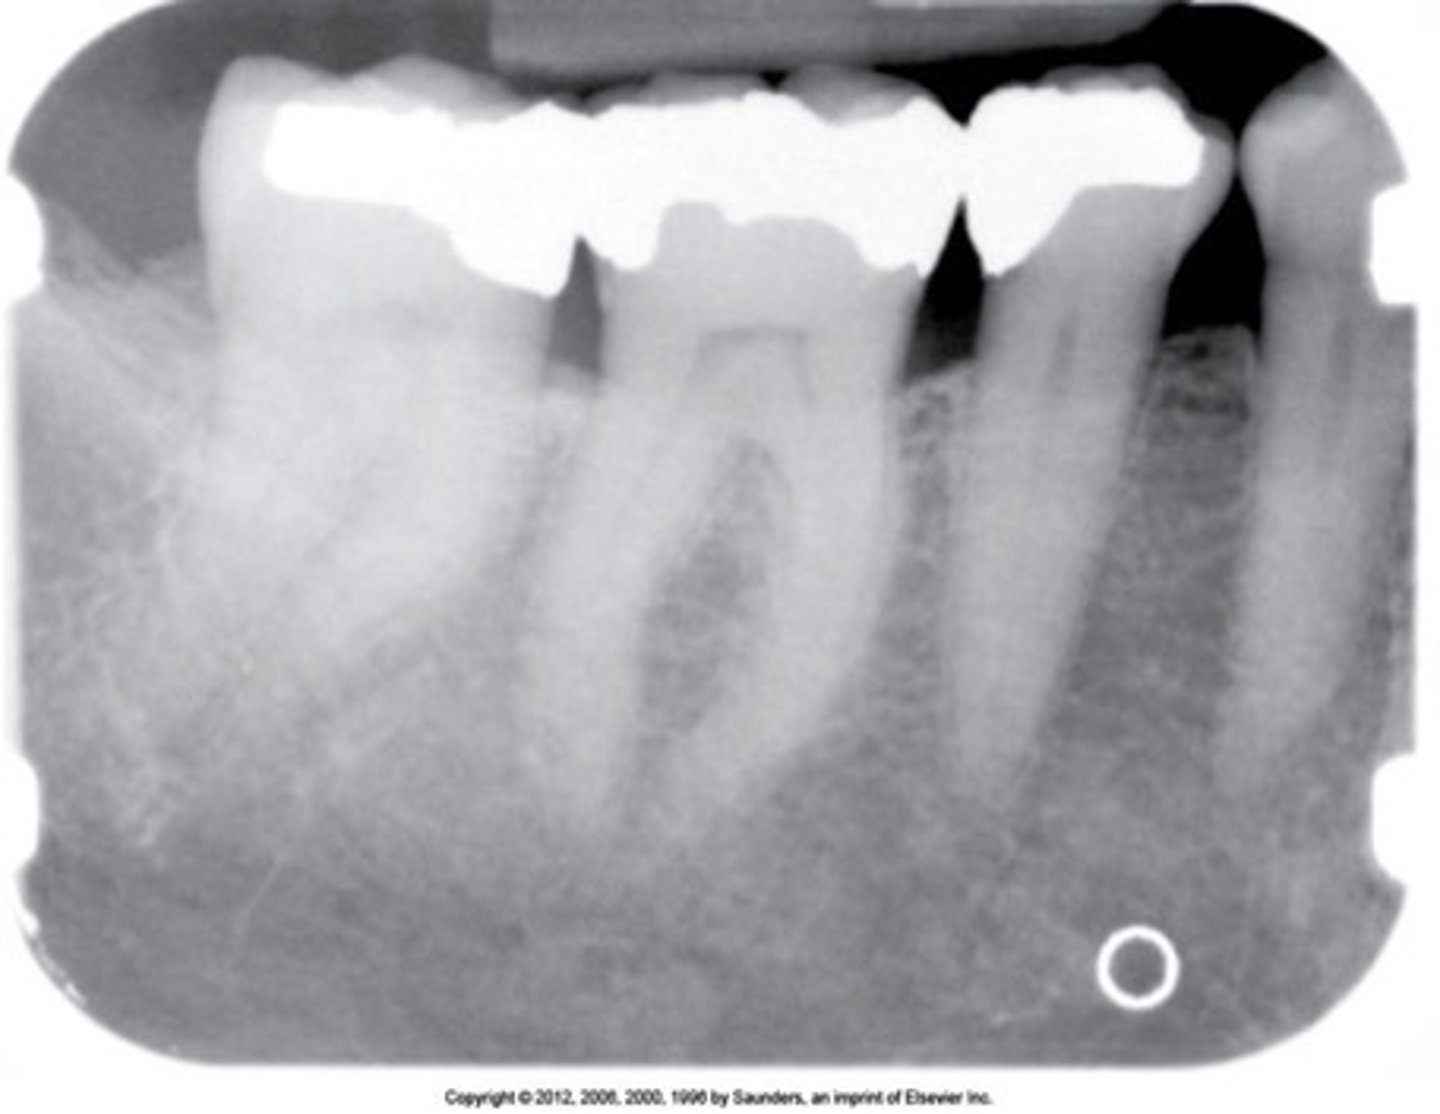

apicoectomy